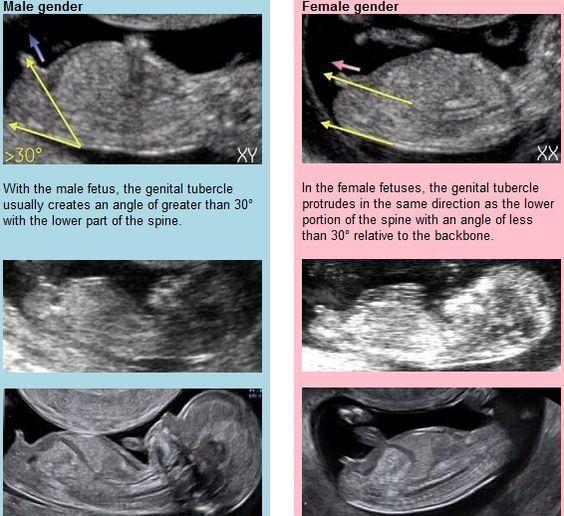

@pavca1982 v tomhle týdnu se to bere z profilu a úplně jinak než na velkém UTZ.. 😉

@michalelka ve 14tt jeste pinda neni 🙂

@michalelka neeee promin, tak jsem to nemyslela - ja jen, kdybys nevedela, spousta holek to nevi, nez na to tady narazi 🙂 Jasne, dr to musel videt lepe, primo kdyz na prcka koukal - ja si nejsem ani jista, jestli to, co na fotce je, je vlastne ten pohlavni hrbolek 🙂 U nekterych fotek to jde videt krasne ciste, tady ne, ale dr bych verila - nam ve 14tt rekli neomylne holku a cekame ji 🙂